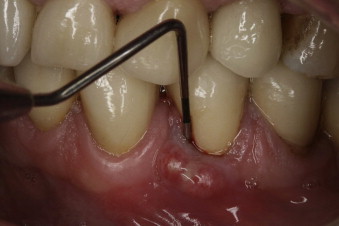

A pocket between the gum and the tooth, near the fracture, where the gum essentially detaches from the tooth

A dental professional or specialist (usually an endodontist) may diagnose a fracture during a root canal procedure if they can see a crack. If the fracture occurs after the procedure, they might need to take X-rays, which may show the fractured root characteristically shaped like the letter J, or the specialist may also use a diagnostic method known as transillumination, where they shine a light through your tooth to detect any fracture lines.